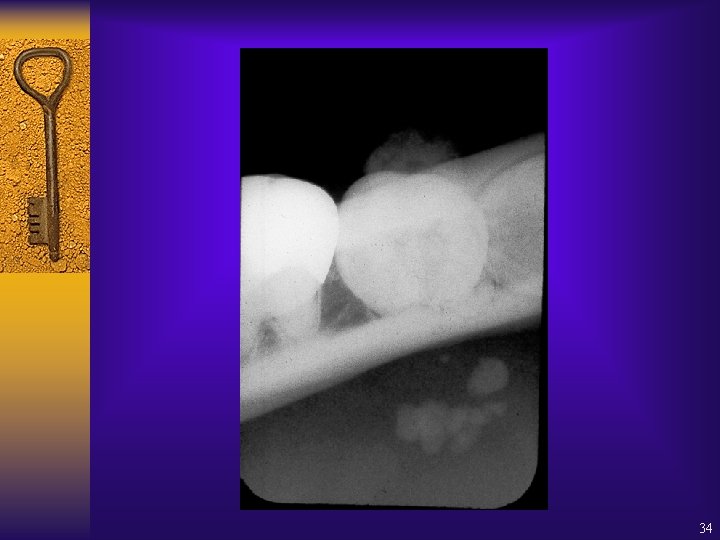

Location of radiopaque lesion 35